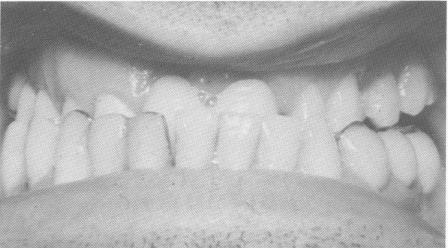

Fig. 15-23. Upon further observation, the incisal edges of the anterior upper and lower teeth almost met when the lower jaw was retruded.

2 Incisal edges of anterior upper, lower teeth when lower jaw retruded